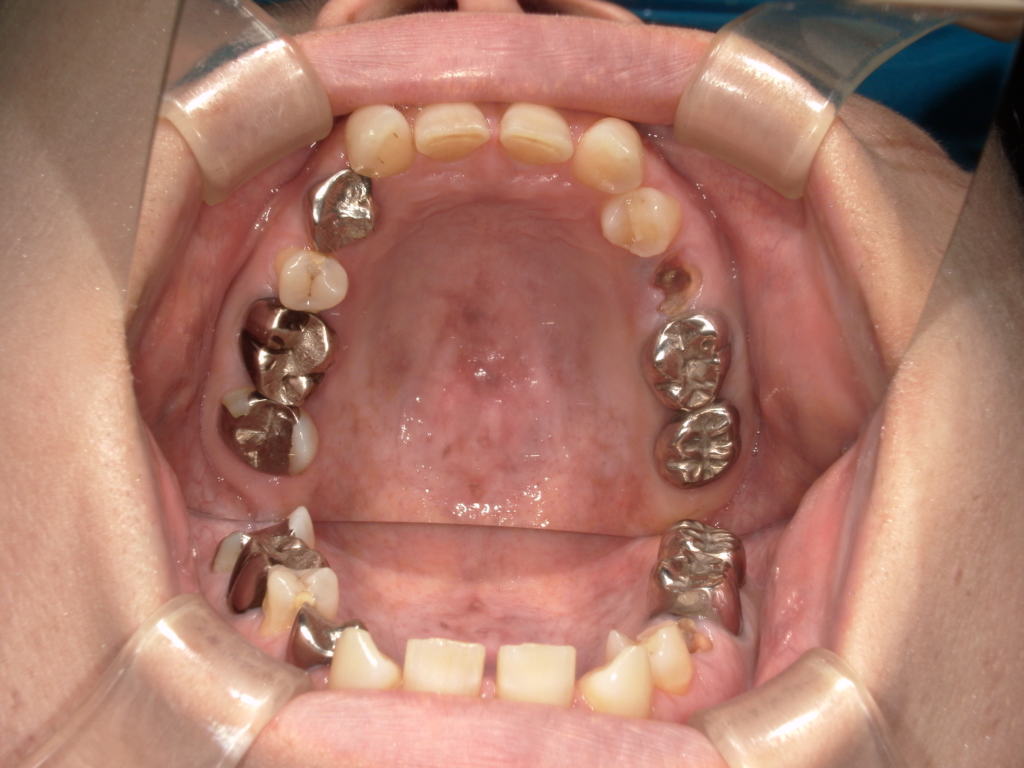

N様 50代 男性 インプラント実例 #37

前歯の4本が、残すのが難しい状況となり、インプラント治療を行いました。

インプラントは前歯に2本埋入し、4本の前歯を作っています。歯を抜くと同時にインプラントを埋入し、仮歯を作りました。その後2ヶ月で、被せ物を入れました。被せ物は、セラミックスで作っています。

治療前

治療後